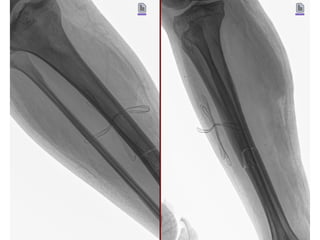

20/09/2025

NOMBRE:MARTINEZ SANCHEZ IVAN

NSS:3906871557 1M1987OR

URGENCIAS A

Edad: 32 AÑOS

Comorbilidades: NINGUNA

Fecha de la lesión: 13/09/25

Mecanismo de lesión: ACCIDENTE EN MOTOCICLETA

Laboratorios: DENTRO DE NORMALIDAD

Valoraciones: NA

Diagnósticos: FRACTURA DIAFISIARIA TERCIO MEDIO DE TIBIA DERECHA EXPUESTA GA II AO 42A1C

Cirugía Proyectada: ASEO QUIRURGICO+ DESBRIDAMIENTO + REDUCCION CERRADA VS ABIERTA CON FIJACION INTERNA CON

COLOCACION DE FIJADORES EXTERNOS VS DCP 4.5 MM A TIBIA DERECHA

Material OSS Solicitado: NA

NOMBRE:MARTINEZ SANCHEZ IVAN NSS:39068715571M1987OR URGENCIAS A Edad: 32 AÑOS Comorbilidades: NINGUNA Fecha de la lesión: 13/09/25 Mecanismo de lesión: ACCIDENTE EN MOTOCICLETA Laboratorios: DENTRO DE NORMALIDAD Valoraciones: NA Diagnósticos: FRACTURA DIAFISIARIA TERCIO MEDIO DE TIBIA DERECHA EXPUESTA GA II AO 42A1C Cirugía Proyectada: ASEO QUIRURGICO+ DESBRIDAMIENTO + REDUCCION CERRADA VS ABIERTA CON FIJACION INTERNA CON COLOCACION DE FIJADORES EXTERNOS VS DCP 4.5 MM A TIBIA DERECHA Material OSS Solicitado: NA